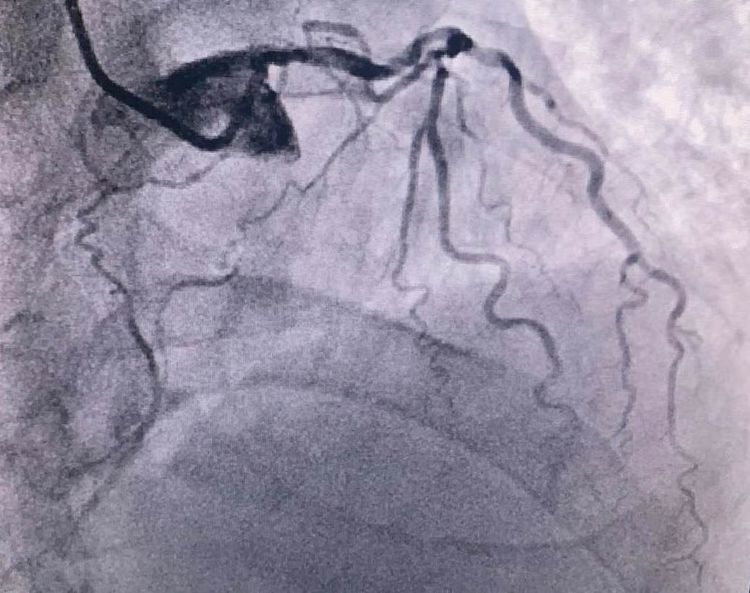

患者前降支、右冠100%闭塞,LCX中段60%狭窄。命悬一线,手术台上持续胸痛。和患者家属及时沟通后,决定行PTCA术。血压低至60/40mmHg,在主动脉内球囊反博的支持下紧急行PCI术。轨道很快建立,导丝也及时通过病变血管,噩梦来了,患者发生室颤了。在吴栋梁院长的指挥下,李阳主任和心脏团队的成员共同努力下,除颤、冠脉内溶栓、多个球囊轮流上阵,患者病情平稳了,罪犯血管及时开通,血流恢复三级血流。平安下台,准备择日再处理冠脉情况。